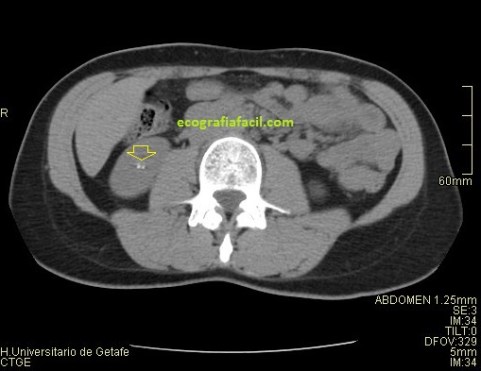

Al realizar la ecografía consigo demostrar una litiasis muy ecogénica con una potente sombra acústica posterior en el polo inferior del riñón derecho. En la petición del especialista se especificaba control de litiasis bilateral, sin embargo, en el otro riñón no había ni resto de litiasis. Pregunté a la paciente si había tenido cólicos nefríticos expulsivos (con expulsión de piedra) desde el último control, su respuesta fue negativa. Dado que tenía controles previos, los consulté, en la última eco realizada, 8 meses atrás no había piedras en el riñón izquierdo, donde yo no había visto en la actualidad, pero ví que entre una y otra ecografía había un TC de Abdomen sin contraste. En el TC se observaban litiasis renales milimétricas, varias, en el seno renal izquierdo, invisibles en la ecografía.

La secuencia de imágenes que has visto es el proceso que ha llevado la paciente, con una ecografía antes del TC con el mismo resultado en cuanto a litiasis que la última que corresponde con las imágenes 6, 7 y 8 donde puedes ver la litiasis renal derecha grande, en el grupo calicial inferior en longitudinal y en transverso. Riñón izquierdo rigurosamente normal, por más que pude buscar, aún a sabiendas de que en el TC habían salido piedras en ese riñón, además, agrupadas en los diferentes grupos caliciales, imágenes 2 y 5, en las reconstrucciones coronales como en los cortes axiales, pero llama poderosamente la atención como junto a la litiasis del RD en el TC, imagen 3, se ven otras dos pequeñas litiasis, imagen 4, que tampoco pude objetivar en la ecografía, ni se vieron en la ecografía anterior. La Rx señala la vista en las ecografías.